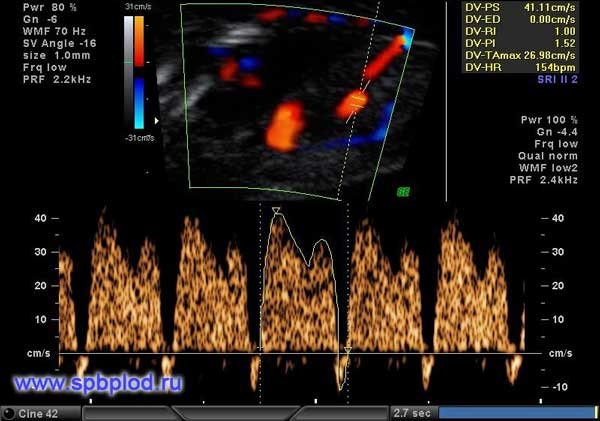

Помимо измерения толщины воротникового пространства и оценки носовой кости, предложено еще несколько маркеров: оценка кровотока через трикуспидальный клапан сердца и через венозный проток, а так же измерение лицевого угла плода. Оценка данных маркеров требует от врача высокой квалификации, и возможна только после получения международной сертификации по каждому маркеру.

Обычно кровь в сосудах плода течет в одном направлении: от сердца к периферическим сосудам. При наличии хромосомной патологии у плода или пороков сердца направление тока крови может изменяться, и в некоторые фазы сердечного цикла кровь начинает течь обратно к сердцу.

Нормальный кровоток в венозном протоке плода в 12 недель беременности

Регистрация кровотока через трикуспидальный клапан сердца и через венозный проток (этот небольшой сосуд есть только у плодов, в периоде новорожденности кровоток в нем прекращается, и он закрывается) позволяет выявить до 65% плодов с болезнью Дауна. У 1-3% нормальных плодов мы также можем увидеть обратный кровоток в венозном протоке или через трикуспидальный клапан, поэтому эти признаки должны оцениваться в комплексе с другими данными ультразвукового исследования.